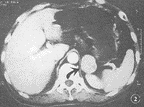

图2 良性非功能性副节瘤 CT强化扫描示肾上区肿瘤(箭头),不均匀强化明显

2.2 病变数目:本组14例均为单发,未见多发。其中呈团块结节者10例(图1,2,5,6),呈连续长块状4例(图4)。

2.3 病变大小:病变最大径<5 cm者6例(图1,2,5,6),其中良性5例,恶性1例;功能性5例,非功能性1例。病变5~10 cm者5例(图3),其中良性4例,恶性1例;功能性1例,非功能性4例。病变>10 cm者3例(图4),均为恶性;功能性1例,非功能性2例。

2.4 病变形态:病变边缘呈光滑圆形结节状3例,均为良性(图1,2,6),有不同程度分叶切迹,或呈分叶不规则状11例(图3,4,5)。

2.7 病变质地:病变密度或信号强度呈均匀者7例(图1,5),不均匀者2例(图2),有明显坏死囊变者5例(图3,4),其中1例有小点钙化。伴有坏死囊变者5例中4例为恶性,1例为良性。

2.8 病变强化特点:5例进行CT强化扫描均表现肿瘤周边部明显强化(图6),其中3例肿瘤内部见不规则强化,2例良性(图2),1例为恶性(图4)。